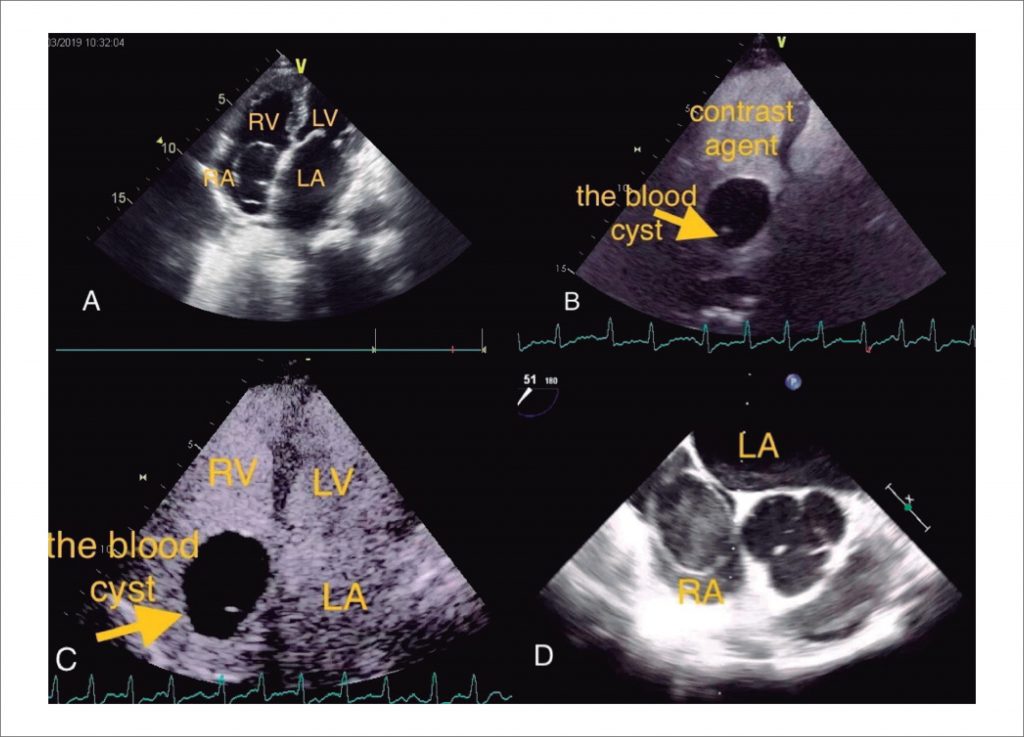

A Case Report of Valvular Heart Disease Complicated with a Blood Cyst in Right Atrium. Review of the Literature

Blood cysts in the heart are often recognized as benign. They usually do not cause clinical symptoms and are often found in infants younger than two months of age. In most cases, blood cysts are attached to cardiac valves or their supporting structures. Cardiac blood cysts in adults are extremely rare, especially in the chambers of the heart. Here, we report a case of valvular heart disease complicated with a blood cyst in the right atrium. Transthoracic echocardiography, contrast echocardiography and esophageal echocardiography were used to examine the patient.